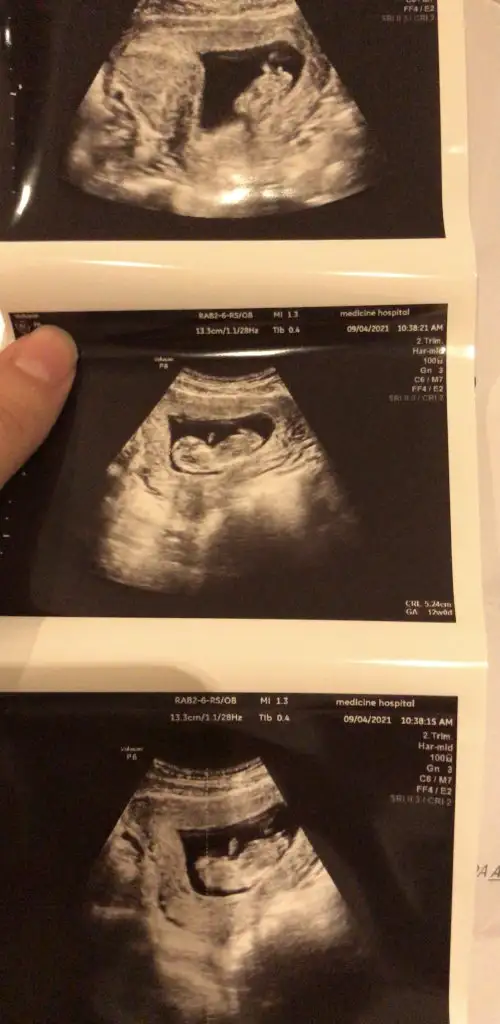

Net değil USG emin olamadımIkra meyra bu görüntümüz var ama sırtı dönük tahmin yapabilecek misin bu ultrasonda canım teşekkürler

Canım bi bakar mısın yandan net görüntü yok maalesef 18 haftalık doktor erkek dedi ikinci resimde işaretlediği kısma pipi dedi sence de erkek mi bundan önce ki doktor kıza benzetmiştiKız gibi

Canım bakar mısın benim attığımı daCanım bi bakar mısın yandan net görüntü yok maalesef 18 haftalık doktor erkek dedi ikinci resimde işaretlediği kısma pipi dedi sence de erkek mi bundan önce ki doktor kıza benzetmişti

Ben 11 12 13 haftalar bakiyorum varsa paylaşınCanım bi bakar mısın yandan net görüntü yok maalesef 18 haftalık doktor erkek dedi ikinci resimde işaretlediği kısma pipi dedi sence de erkek mi bundan önce ki doktor kıza benzetmişti